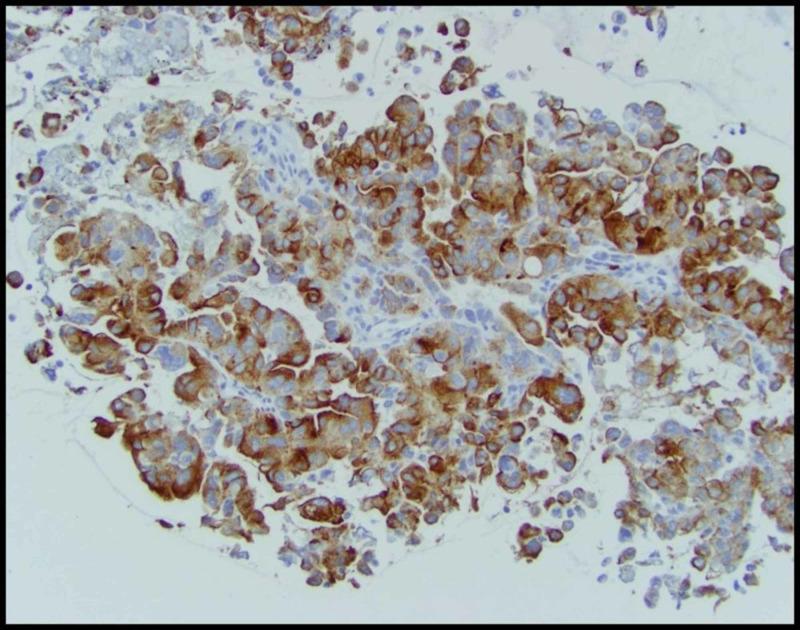

Renal cell carcinoma (RCC) can present with a myriad of clinical symptoms and signs. It is also notorious for its initial presentation with distant metastasis. We report a case of a 42-year-old male diagnosed with papillary RCC (PRCC) presenting with pleural and nodal metastases in the absence of a radiographically-detected tumor primary. PRCC was diagnosed on immunohistochemical analysis of the tissue from the pleura and mediastinal lymph nodes and confirmed by gene expression profiling studies. As per treatment guidelines for metastatic RCC, the patient was started on sunitinib with evidence of disease progression after two cycles and palliative care approach was recommended due to rapidly declining performance status. Prospective data on the optimal management of metastatic PRCC are lacking, but drugs used are similar to the treatment of clear cell carcinomas (vascular endothelial growth factor (VEGF) tyrosine kinase inhibitors, mammalian target of rapamycin inhibitors) and checkpoint inhibitors. Further molecular study of these rare tumors is warranted to detect drivers of oncogenesis and identify targets for therapeutic intervention.

摘要